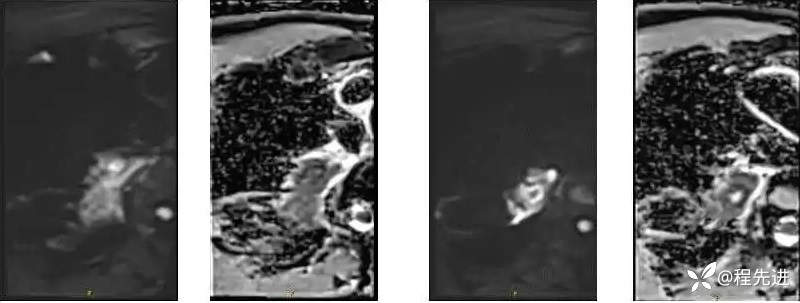

DWI 、ADC :